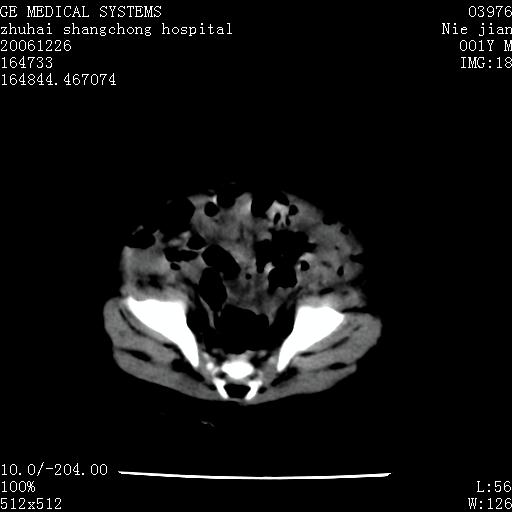

3个月婴儿腹胀来看。

【影像特征】

1、肝明显增大,肝弥漫性低密度灶。

2、肾上腺区见类圆形肿块,其内密度不均,见片状偏高密度。

【诊断】

1、肝弥漫性病变,考虑急性肝炎致广泛脂肪浸润可能性大。

2、肾上腺区占位,假性肿瘤?肾上腺血肿(感染所致)?